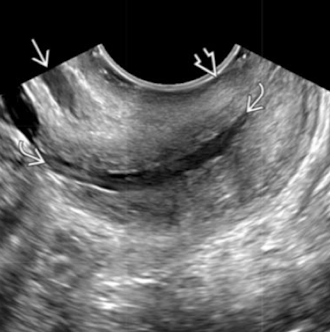

SONO: cervical cerclage

post-cerclage procedure; imaged transvaginally

cerclage stitches are echogenic with posterior shadowing

serial scans may be done to ensure cerclage remains secure and cervix is closed

what are the arrows pointing to?

cervical cerclage stitches